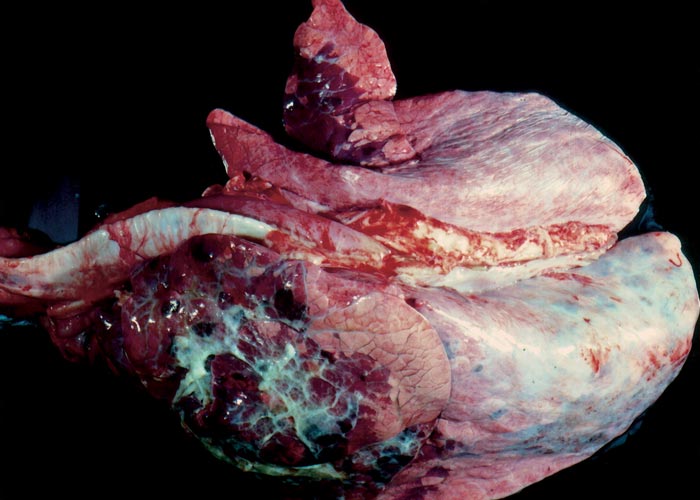

Bronchopneumonia and fibrinous pleuritis due to secondary bacterial infection are present in some cases (Figure 8). Conjunctivitis also is a common feature of MD.

Respiratory tract disease

Bovine viral diarrhoea-associated disease of the respiratory tract depends on the presence and effect of opportunistic pathogens.178 Typically, severe fibrinous pleuropneumonia develops in animals suffering from combined M. haemolytica and BVDV infections179, 182 (Figure 8). Primary uncomplicated respiratory tract disease may include interstitial mononuclear pneumonia, alveolar epithelial necrosis and haemorrhage.147